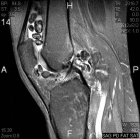

26 year old female with ten year history of right knee pain with intermittent swelling